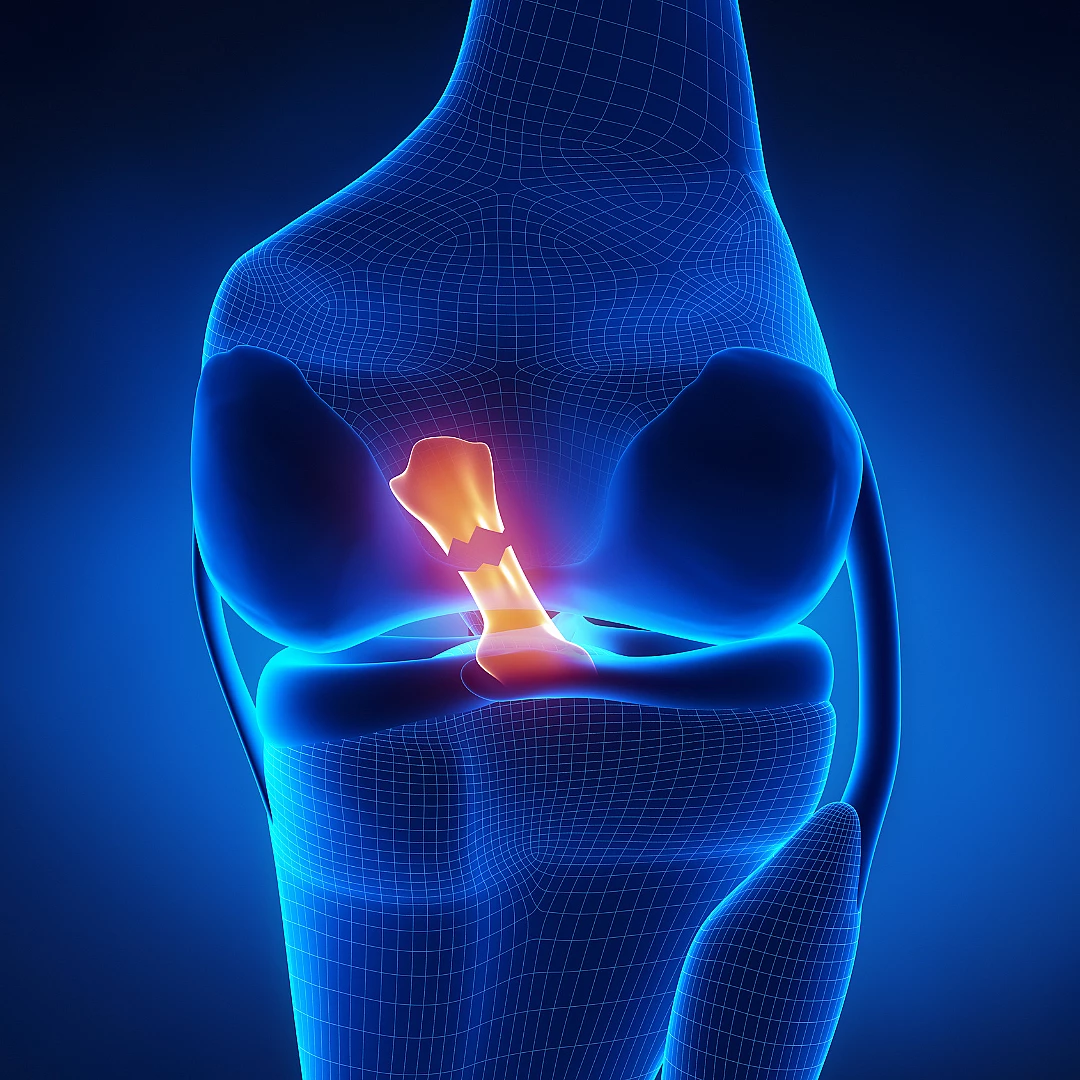

علاج اصابات الرباط الصليبي

إصابات الرباط الصليبي هي من أكثر إصابات العظام شيوعًا، خاصةً بين الرياضيين.

تختلف طرق العلاج وفقًا لحالة المريض واحتياجاته، وتنقسم إلى نوعين: تحفظي وجراحي.

• العلاج التحفظي يعتمد على الحماية، والدعامة، والتمارين لتقوية العضلات المحيطة

• العلاج الجراحي مخصصًا للحالات المتقدمة والرياضيين، حيث يتم استبدال الرباط بآخر من أنسجة المريض أو ببديل آخر

• تحقق الجراحة نسبة نجاح عالية، وتعتمد هذه النسبة على العديد من العوامل المحيطة بالجراحة

• يمكن للمريض العودة إلى نشاطاته الرياضية بعد العلاج

إعادة ترميم الرباط الصليبي بالمنظار

إعادة ترميم الرباط الصليبي هو الحل الجراحي الأنسب لحالات القطع التي لم تستجب للعلاج التحفظي.

• في حالة الإصابة عند الرياضيين يفضل إجراؤها على أيدي مختصين متمرسين في علاج الإصابات الرياضية

• نسبة نجاح عالية تساهم في العودة إلى النشاط البدني السابق

• إستخدام الأربطة من نفس المريض أو من مصدر أخر حسب الحالة

• مدة التعافي: تستغرق من ٦ إلى ١٢ شهرًا

التأهيل الجيد والمتابعة الحثيثة هما من أهم ركائز النجاح.